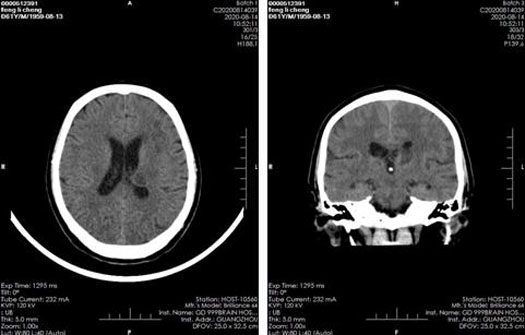

影像检查:

2020年8月14日CT结果显示:左侧丘脑-基底节脑出血较前明显吸收。